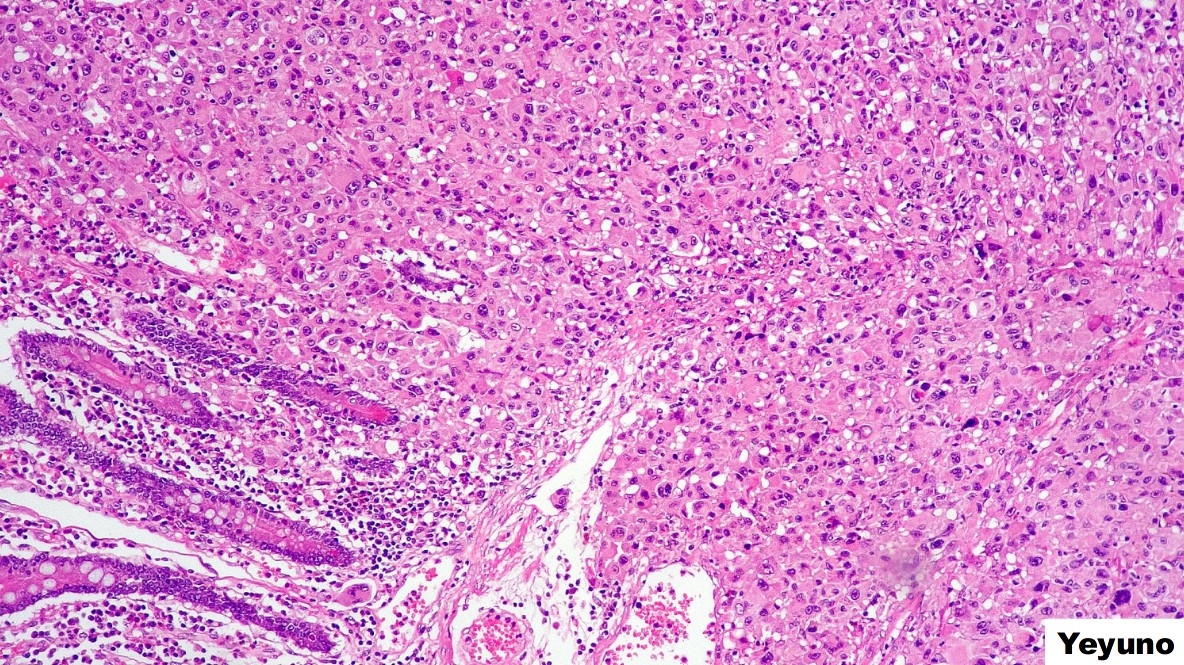

PREGUNTA 2

El tumor en yeyuno presenta una morfología epitelioide con crecimiento submucoso, por los hallazgos microscópicos se debe pedir lo siguiente:

A) MLH-1, MSH-2, MSH-6, PMS-2, P53

B) CD117, DOG-1, CD34, S100 Y ACTINA

C) CD45, CD20, CD3, VEB, ALK, CD30

PREGUNTA 3

El tumor de yeyuno sólo expresa s100, por lo que harías lo siguiente:

A) El diagnóstico es un GIST epitelioide.

B) Ampliaría batería de inmunohistoquímica para descartar un tumor histiocítico o de células dendríticas

C) Buscaría marcadores melanocíticos y agregaría BRAF.